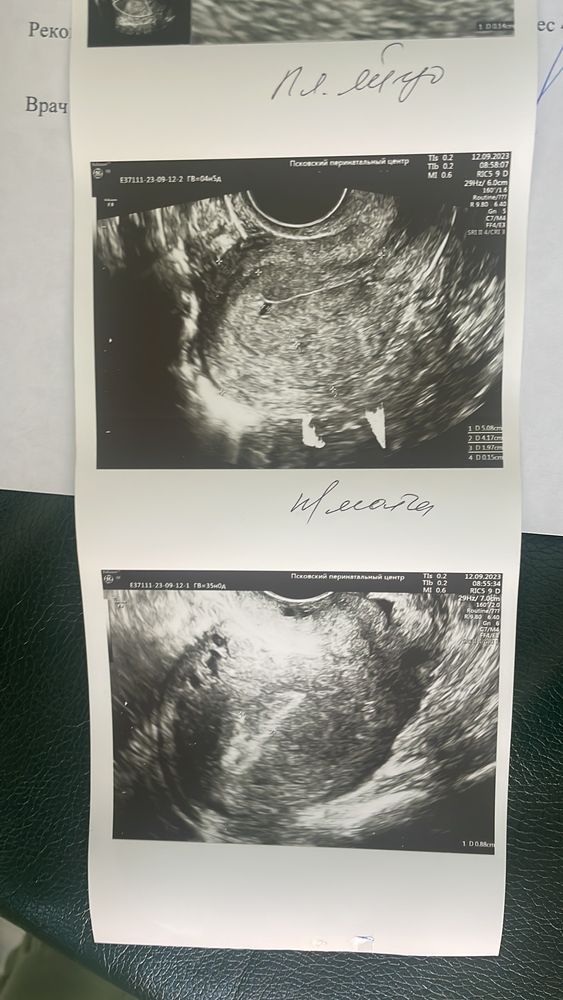

Сделала узи и хгч …

Что-то здесь не то, соглашусь со всеми ниже при таком маленьком хгч невозможно найти ПЯ

Не понимаю, откуда на узи плодное яйцо при хгч чуть больше 100 👀

ПЯ можно увидеть при хгч от 1000-1500

Юлия, у вас хгч 133. При таком значение просто невозможно ничего обнаружить . Сдайте в динамики хгч. Когда будет хгч от 1000 смело идите на узи.

Пушинка, хгч был 52,3 , 114,7, 133,7 прирост маленький .. Что тогда показалось фиг знает

Навряд ли на узи увидели плодное яйцо. Скорее всего бхб(

передайте хгч в другом месте, лаба могла ошибиться при хгч 133 ну невозможно никак ПЯ найти

реально какойто полный бред, хгч 100 и ПЯ???у вас тест то еще с контрольной полоской не сравнялся.

ПЯ видно при хгч от 1000. У вас навнрно ошибка лаборатории. Сдайте хгч в другой.